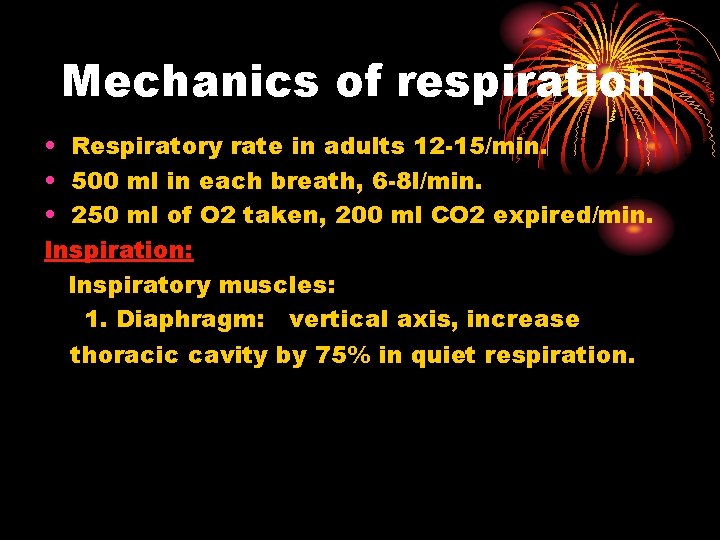

Mechanics of respiration • Respiratory rate in adults 12 -15/min. • 500 ml in each breath, 6 -8 l/min. • 250 ml of O 2 taken, 200 ml CO 2 expired/min. Inspiration: Inspiratory muscles: 1. Diaphragm: vertical axis, increase thoracic cavity by 75% in quiet respiration.

2. External intercostal muscles: anteroposterior diameter, 10% only. 3. Accessory inspiratory muscles: act in forcible respiration: scalene and sternocleidomastoid muscles. Mecahnics Contraction of insp. muscles decreases intrapleural pressure from – 2. 5 mm Hg to – 6 mm. Hg : by increasing the thoracic cavity the lungs will move with the thoracic cage as the parietal and visceral pleurae are in contact, the pressure in airways decreases, leading to entry of air from outside.

• In forcible insp. intrapleural pressure reaches – 30 mm Hg Expiration: • Passive process due to elastic recoil of insp. muscle and lungs leading to increased press. in airways and outflow of air. • Accessory expiratory muscles work in forced expiration: abdominal muscles and internal intercostal.